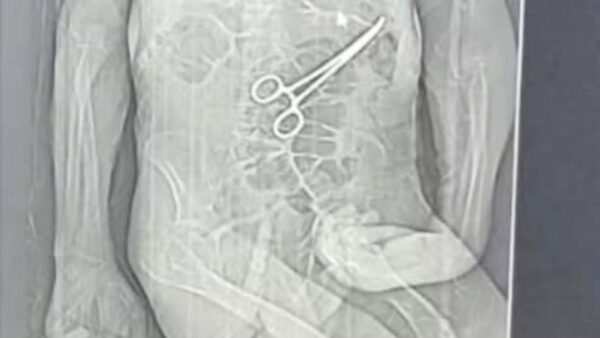

A família de Manoel Cardoso de Brito, de 68 anos, acusa o Hospital Municipal de João Pinheiro, no Noroeste de Minas Gerais, de erro médico após o idoso morrer na véspera do Natal. Segundo os parentes, uma pinça cirúrgica foi esquecida dentro do corpo do paciente após a primeira cirurgia, fato que, segundo os familiares, só veio à tona depois do óbito.

Segundo o advogado da família do idoso, Iuri Evangelista Furtado, as medidas legais começaram a ser adotadas depois que um exame de tomografia, divulgado por uma rádio local, chegou ao conhecimento de parentes. A imagem indicaria a presença do instrumento cirúrgico no corpo do paciente.